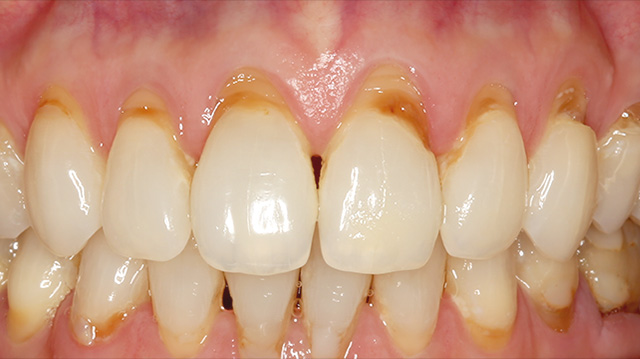

| 年代・性別 | 50代 男性 |

|---|---|

| 主訴 | 前歯を綺麗にしたい |

| 治療回数 | 3回 |

| 治療期間 | 約1ヶ月 |

| 費用 | 仮歯 5,500円 ジルコニアクラウン 176,000円 |

*キャンセルポリシーをご一読のうえご予約ください